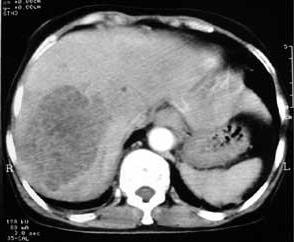

3.CT檢查CT檢查可發現膿腫的大小及形態,顯示膿腫在肝臟中的確切部位,為臨床醫師行膿腫穿刺及手術引流提供清晰、直觀的影像資料。主要表現為肝內出現低密度區,CT值略高於肝囊腫,邊界多數不太清晰,有時低密度區內可出現塊狀影。注射造影劑後其外圍增強明顯,邊界更加清楚。增強掃描的典型表現是膿腫壁的環狀增強(靶征),出現“靶”征強力提示膿腫已形成。